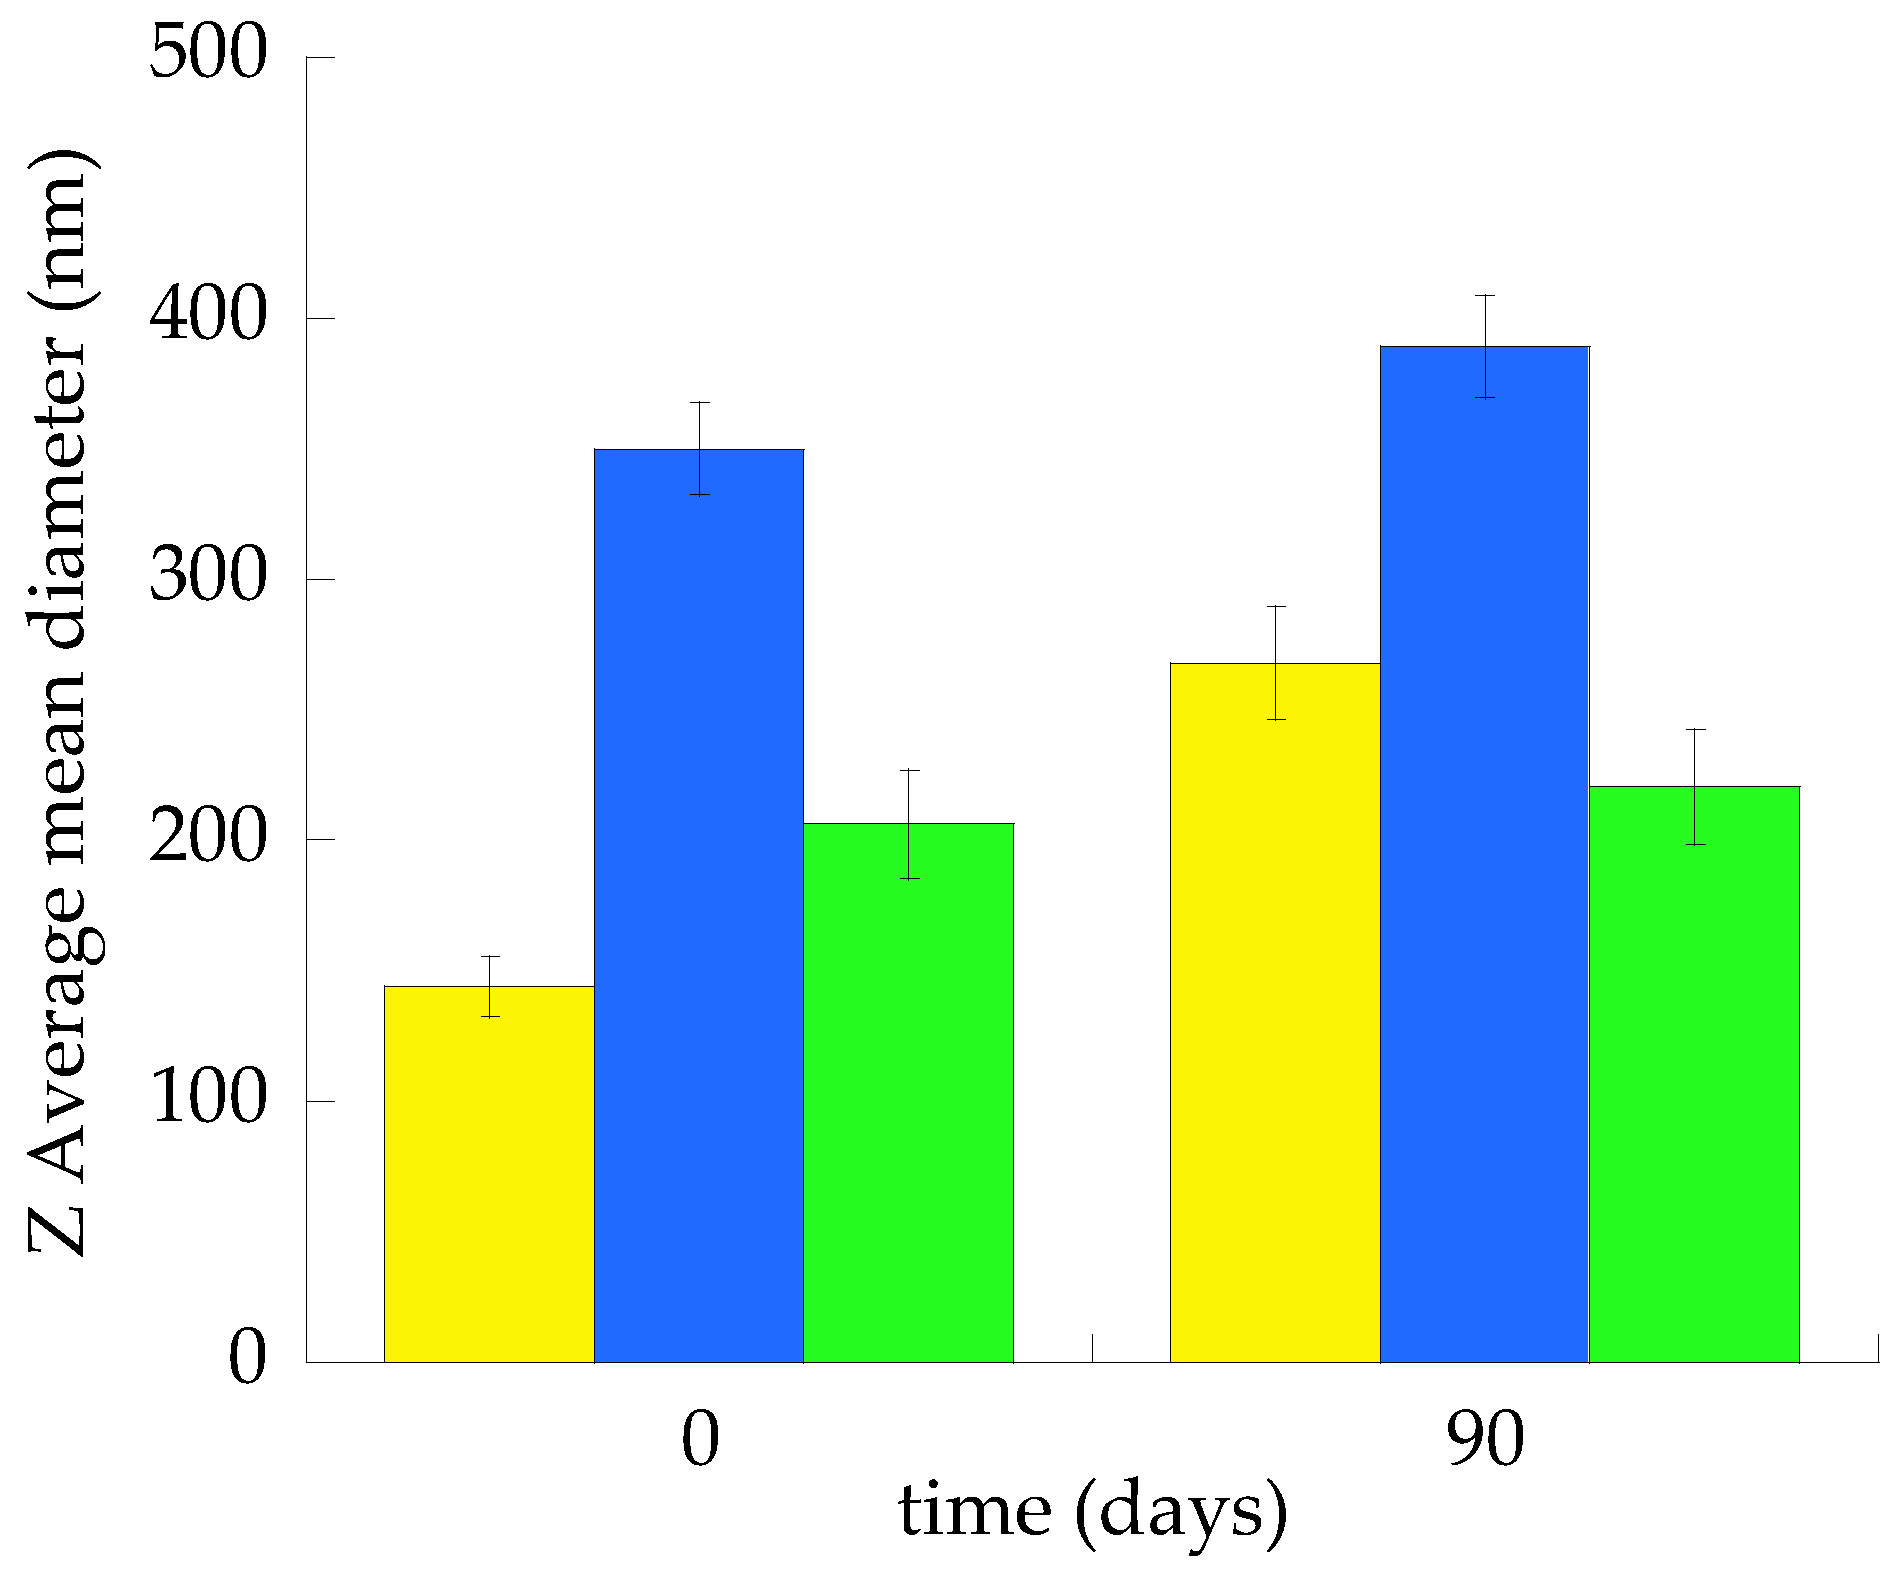

2.2.1. Size Distribution

| Z-Average (nm) 1 ± s.d. | 206.32 ± 33.22 | 146.21 ± 10.21 | 350.40 ± 23.61 |